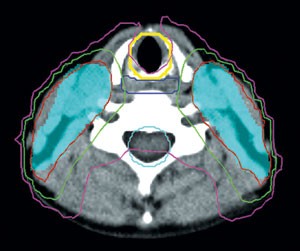

To improve locoregional tumor control and survival in patients with locally advanced head and neck cancer (HNC), therapy is intensified using altered fractionation radiation therapy or concomitant chemotherapy. However, intensification of therapy has been associated with increased acute and late toxic effects. The application of advanced radiation techniques, such as 3D conformal radiation therapy and intensity-modulated radiation therapy, is expected to improve the therapeutic index of radiation therapy for HNC by limiting the dose to critical organs and possibly increasing locoregional tumor control. To date, Review articles have covered the prevention and treatment of radiation-induced xerostomia and dysphagia, but few articles have discussed the prevention of hearing loss, brain necrosis, cranial nerve palsy and osteoradionecrosis of the mandible, which are all potential complications of radiation therapy for HNC. This Review describes the efforts to prevent therapy-related complications by presenting the state of the art evidence regarding advanced radiation therapy technology as an organ-sparing approach.

Xerostomia can be reduced by limiting the mean dose to 26 Gy for one parotid gland, ≤39 Gy to the noninvolved submandibular glands and ≤30 Gy to the oral cavity

Late dysphagia can be reduced by keeping the mean dose ≤50 Gy to the non-involved pharyngeal constrictor muscles and the larynx